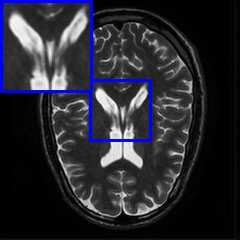

Limited by imaging systems, the reconstruction of Magnetic Resonance Imaging (MRI) images from partial measurement is essential to medical imaging research. Benefiting from the diverse and complementary information of multi-contrast MR images in different imaging modalities, multi-contrast Super-Resolution (SR) reconstruction is promising to yield SR images with higher quality. In the medical scenario, to fully visualize the lesion, radiologists are accustomed to zooming the MR images at arbitrary scales rather than using a fixed scale, as used by most MRI SR methods. In addition, existing multi-contrast MRI SR methods often require a fixed resolution for the reference image, which makes acquiring reference images difficult and imposes limitations on arbitrary scale SR tasks. To address these issues, we proposed an implicit neural representations based dual-arbitrary multi-contrast MRI super-resolution method, called Dual-ArbNet. First, we decouple the resolution of the target and reference images by a feature encoder, enabling the network to input target and reference images at arbitrary scales. Then, an implicit fusion decoder fuses the multi-contrast features and uses an Implicit Decoding Function~(IDF) to obtain the final MRI SR results. Furthermore, we introduce a curriculum learning strategy to train our network, which improves the generalization and performance of our Dual-ArbNet. Extensive experiments in two public MRI datasets demonstrate that our method outperforms state-of-the-art approaches under different scale factors and has great potential in clinical practice.